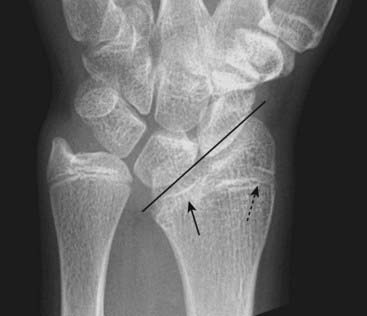

Figure 22-26 Avascular necrosis of the proximal pole of the scaphoid.

A close-up frontal view of the wrist demonstrates that the proximal pole of the scaphoid (solid black arrow) is denser than the distal pole (solid white arrow). There is a fracture through the waist of the scaphoid (dotted white arrow). Because of the peculiar blood supply of the scaphoid (from distal to proximal), fractures through the waist may interrupt the proximal blood supply while the other bones of the wrist, having normal blood supply, become demineralized. This makes the proximal pole of the scaphoid appear denser relative to the other bones of the wrist.